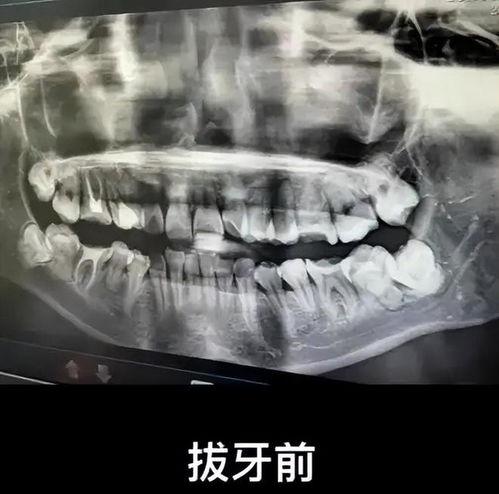

女子拔错牙后坠亡事件:涉事医生被停诊,真相仍待揭开 作为一名关注热点事件的自媒体作者,我深入了解了安徽女子因拔错牙坠亡的事件始末。通过多方信息汇总,我发现这起悲剧背后涉及医疗失误、心理压力以及制度漏洞等多重因素。如今,涉事医生已被通报批评并暂停门诊三个月,但最终调查结果尚未出炉。希望通过本文的剖析,能引起更多人对医疗安全的关注。 腾讯热点 2025年03月27日 02:05 0 点赞 0 评论 63 浏览